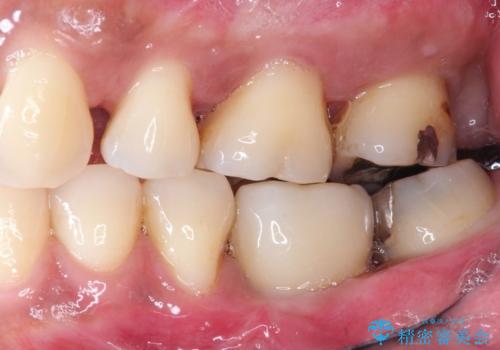

奥歯の根の又の部分の歯周病(=分岐部病変)が進行してしまった場合、

・掃除をしながら様子をみる

・歯の形態を修正し清掃性の向上をはからう

・歯を分割し小臼歯形態×2で補綴する(確定外科が必要)

・より病変の影響を強く受けている方の根だけ抜去し、残った根を温存する

など多様な治療の選択肢があります。

ケースによりますが、いずれの場合も不安要素をかかえたまま歯を温存することになるため、それらを取り除く・かつ感染源を取り除くために歯を抜去するのも効果的な治療法といえます。